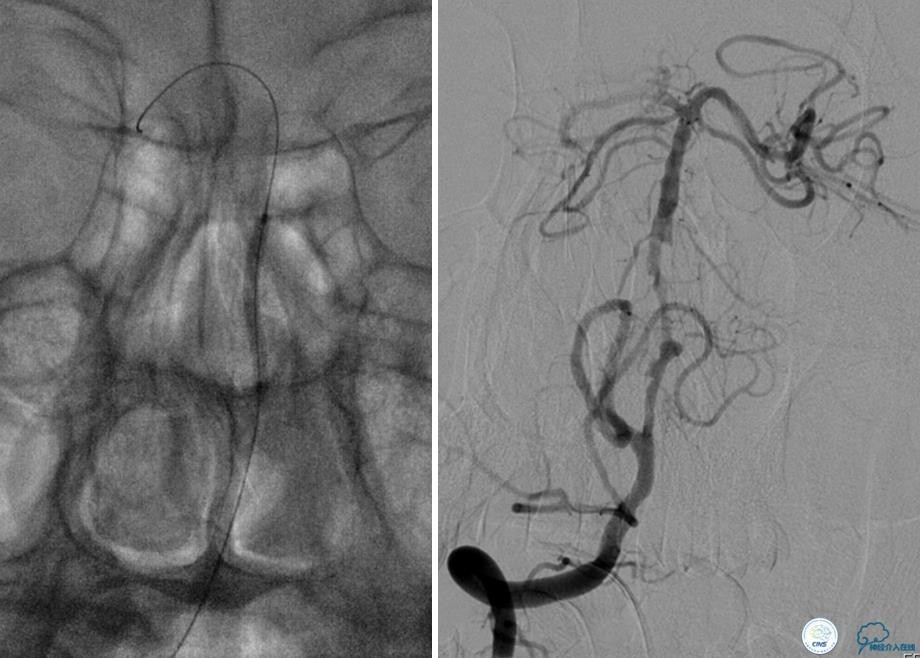

患者:49岁男性,左侧偏瘫1个月,药物治疗、康复训练效果不好,转我院,肌力0~1级。

core-clilnical明显不匹配,是介入开通的合适患者。

造影评价血管、判断闭塞段,微导丝小心穿过闭塞段,微导管造影,交换技术,球囊扩张,Enterprise支架。在后扩张时导丝刺破M3段血管,蛛网膜下腔出血(SAH)。

微导管进入破裂血管,栓塞弹簧圈1枚,出血停止,结束手术。继续双抗,术后2天肌力2级,神经功能恢复明显加快。

术后即刻和6天后CT,患者无明显临床症状。

半年后复查造影,无支架内再狭窄,可见弹簧圈,患者恢复至自己柱杖行走。